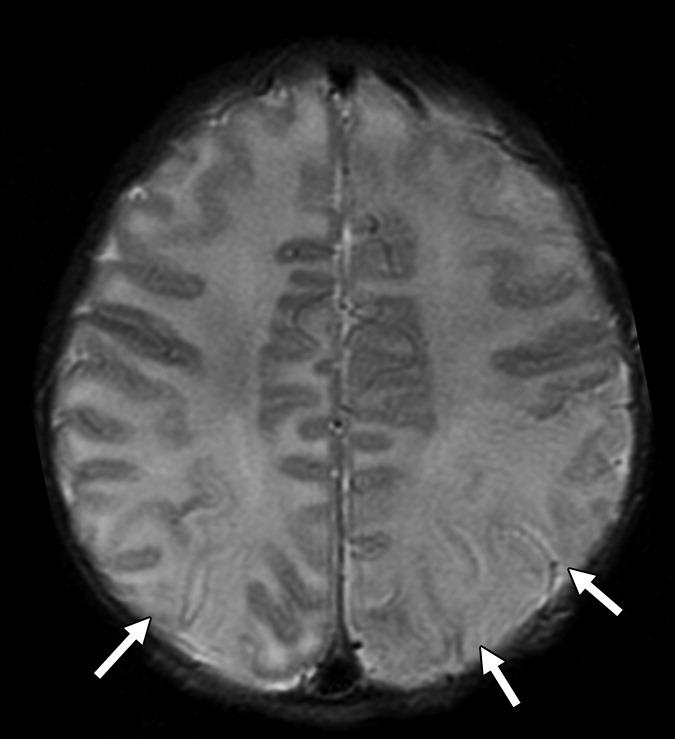

С рождения наблюдалась везикулезная сыпь в области лба. На аксиальной Т2-взвешенной томограмме определяется «missing cortex» симптом: потеря нормального изменения сигнала от коры (кора и белое вещество неразличимы) в обеих затылочных областях, больше слева.

Герпетический энцефалит у младенцев характеризуется более диффузным поражением, причем эти изменения сложнее заметить на фоне незавершенной миелинизации; поражение типично затрагивает кору полушарий, глубокие слои белого вещества, включая перивентрикулярные области и таламусы. Медиальные области височных и нижние области лобных долей часто интактны. Геморрагии встречаются реже и появляются в более поздних стадиях.

Сигнальные характеристики аналогичны энцефалиту у взрослых:

- области повышенного сигнала в Т2-взвешенных последовательностях могут быть плохо заметными на фоне незрелой миелинизации;